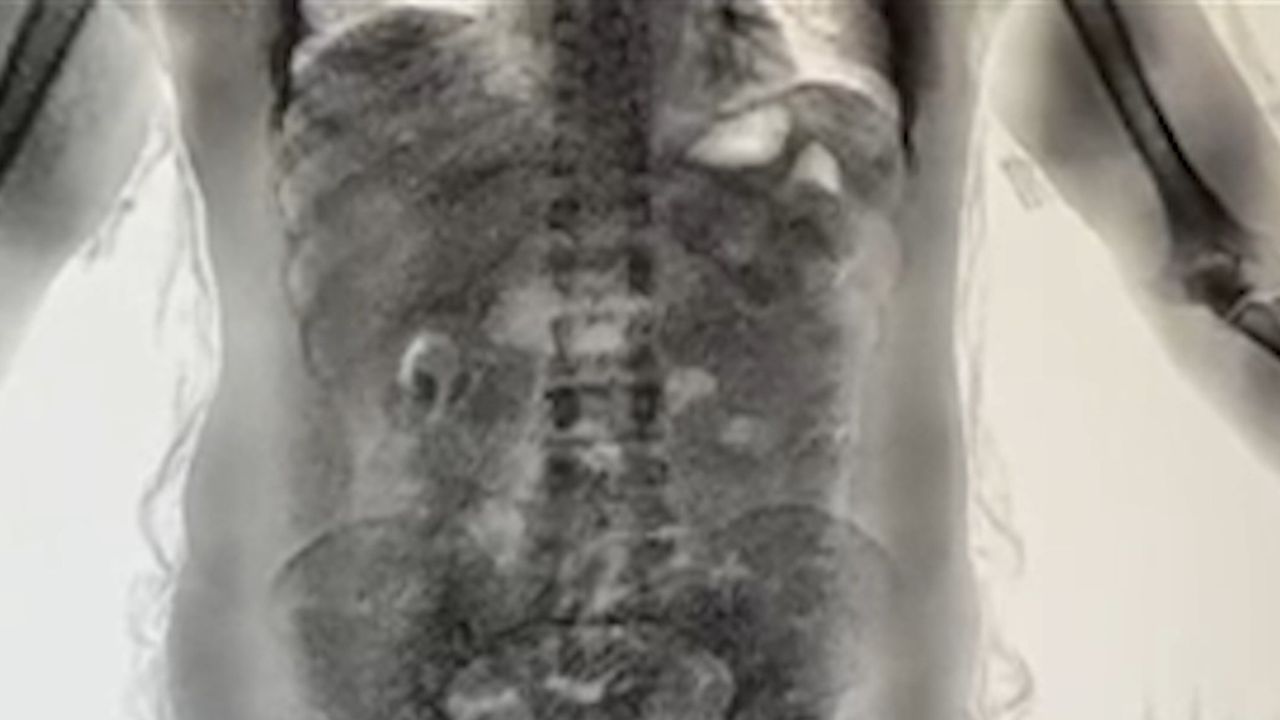

DHA muhabirine yapılan değerlendirmede, riskli ülkelerden gelen yolcuların ekipler tarafından yakın takibe alındığı belirtildi. Uçağın kapısından itibaren terminal içerisinde riskli görülen yolcular, ekipler ve güvenlik kameraları tarafından anbean izleniyor. Şüpheli kişiler gümrük ekiplerince durdurulduktan sonra ilk olarak bagajları aranıyor. Yapılan aramalarda herhangi bir bulguya rastlanmaması halinde, hal ve tavırlarından şüphelenilen yolcular 'yutucu tespit cihazlarının' bulunduğu bölüme götürülüyor. Burada yapılan röntgen incelemesinde, şüphelilerin mide ve bağırsaklarında uyuşturucu madde bulunduğu tespit ediliyor.

2025 yılında İstanbul Havalimanı’nda yürütülen risk analizleri ve etkin denetimler kapsamında 100’ün üzerinde şüpheli yolcu kontrol edildi. Yapılan incelemeler sonucunda 'yutucu kurye' olduğu belirlenen 24 yolcu hakkında adli işlem başlatıldı. Yakalamalarda ağırlıklı olarak kokain cinsi uyuşturucu madde ele geçirilirken, 2025 yılı boyunca 'yutucu kurye' yöntemiyle toplam 29,7 kilogram uyuşturucu maddeye el konuldu.